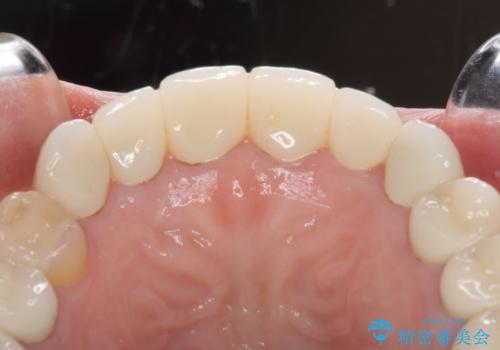

期間と費用はかかりましたが、気になっていた部分全てを改善でき、患者様には大変満足していただきました。